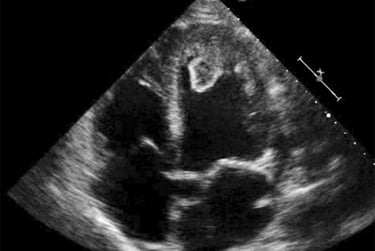

We begin by establishing a shared visual language: cardiac anatomy as it appears on the screen, with careful attention to orientation, probe position, and spatial relationships.

Scanning starts early. Learners rotate through short, focused scan sessions with faculty at the bedside, repeating views and refining technique until confidence builds naturally.

Once images stabilize, physiology is layered in. Wall motion, valve function, timing, and Doppler are introduced only after the image makes sense.